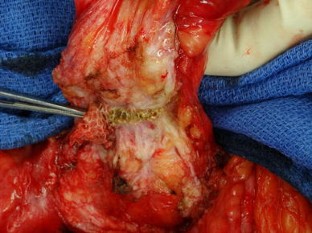

Mesh ingrowth with concomitant bacterial infection resulting in inability to explant: a failure of mesh salvage

Removal is the standard treatment for mesh infection following prosthetic hernia repair. However, certain types of mesh may be less amenable to removal even in the setting of active infection; we present four such cases, all involving the same composite mesh.

Four high-risk patients underwent Parietex mesh implantation for large ventral wall hernias and developed subsequent Staphylococcus infections with attempted explantation of infected mesh and wound care.

There was inability to completely explant mesh in all four cases, leading to chronic purulent wounds and long-term complications.

While mesh infection is a recognized complication of prosthetic hernia repair, many synthetic meshes form a slimy biofilm and thus can be removed relatively easily. However, the structural qualities of certain types of mesh create ingrowth into tissues even in the setting of infection, resulting in inability to explant with subsequent long-term chronic wound complications.